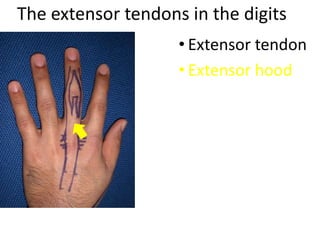

- It describes flexor tendon zones, extensor compartments, and pulley system anatomy.